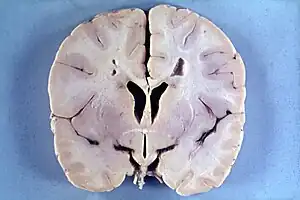

| Brain of a 4-year-old boy with Alexander disease showing macroencephaly and periventricular leukomalacia (note brownish discoloration around the cerebral ventricles) | |

Alexander disease belongs to leukodystrophies, a group of diseases that affect the growth or development of the myelin sheath. The destruction of white matter in the brain is accompanied by the formation of fibrous, eosinophilic deposits known as Rosenthal fibers.[2][6][7] Rosenthal fibers appear not to be present in healthy people,[6][8] but occur in specific diseases, like some forms of cancer, Alzheimer’s, Parkinson’s, Huntington’s, and ALS.[6][8][9] The Rosenthal fibers found in Alexander disease do not share the distribution or concentration of other diseases and disorders.[6]

Alexander disease causes the gradual loss of bodily functions and the ability to talk. It also causes an overload of long-chain fatty acids in the brain, which destroy the myelin sheath. The cause of Alexander disease is a mutation in the gene encoding GFAP.[2][6][3][4][10][9]